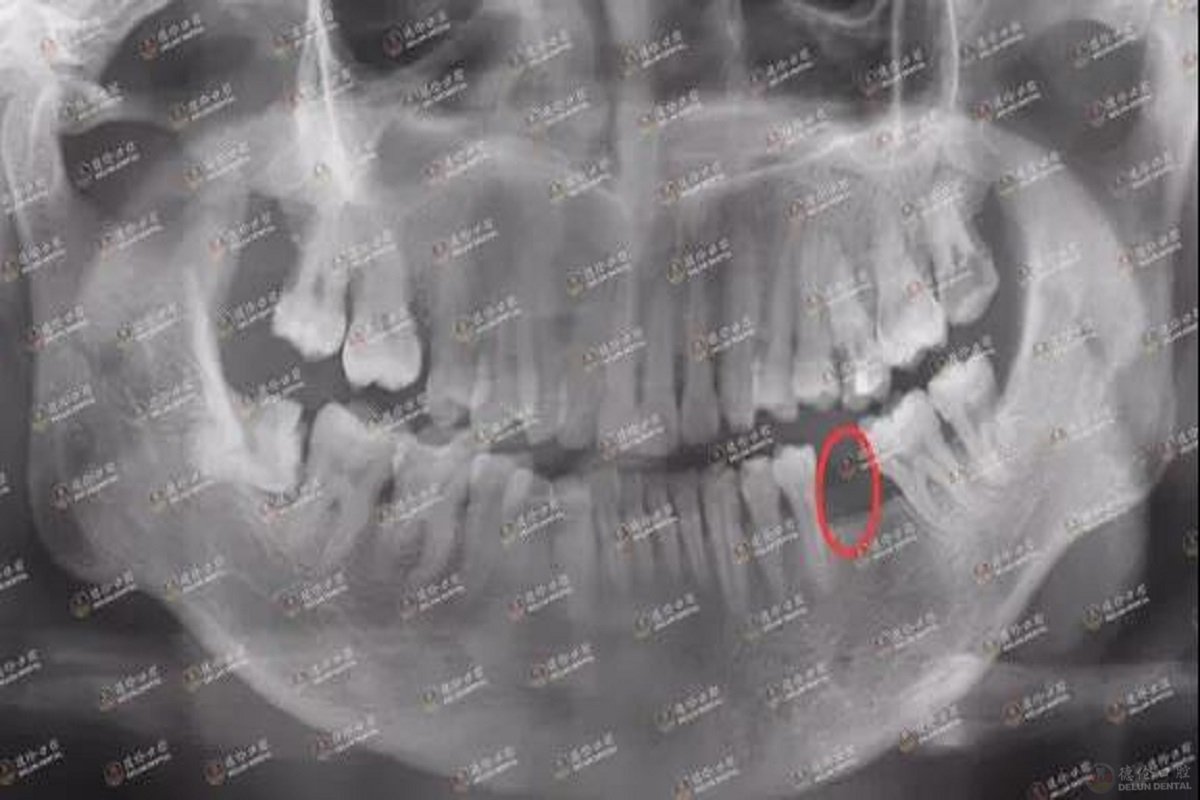

谢先生术前牙齿X光片,下颌缺牙一颗

谢先生的3D数字化导板设计及模拟种牙